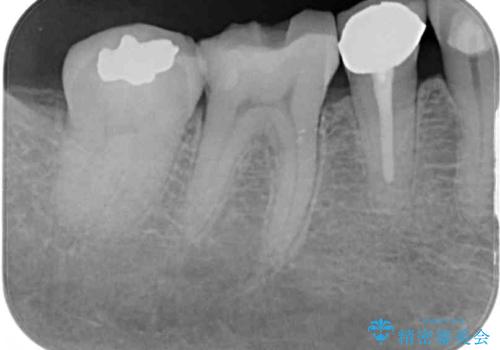

- セラミックが剥がれたり、歯質が欠けたりした奥歯を気にして来院された患者様です。

咬合力が強い方であったため、2歯をフルジルコニアクラウンにて補綴することとしました。

高強度のジルコニアクラウンとしたことで、強い咬合力でも壊れず、審美性を維持しやすい治療を行うことができました。